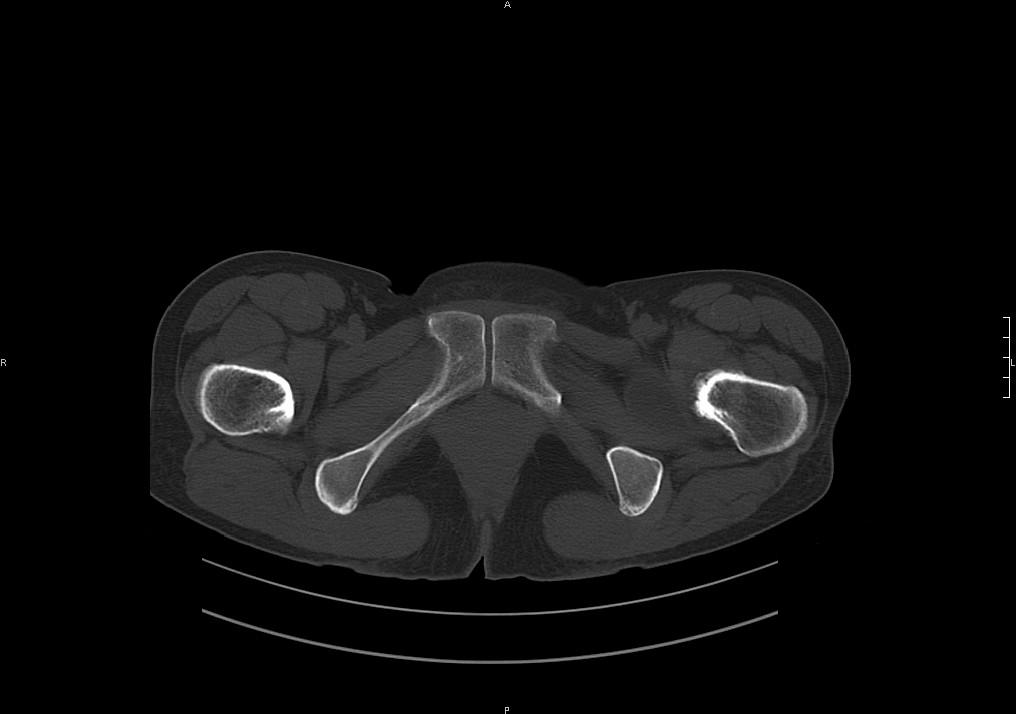

标题: CT19780左髋关节疼痛伴跛行1年,加重1个月。无菌性坏死? [打印本页]

标题: CT19780左髋关节疼痛伴跛行1年,加重1个月。无菌性坏死?

陈旧性骨折啊!

支持陈旧性骨折,结合病史加重一个月,考虑缺血性坏死初期。

髋臼平浅,股骨头覆盖率减小,考虑双侧髋关节发育不良伴退行性变。

股骨颈陈旧性骨折

髋关节退行性骨关节病